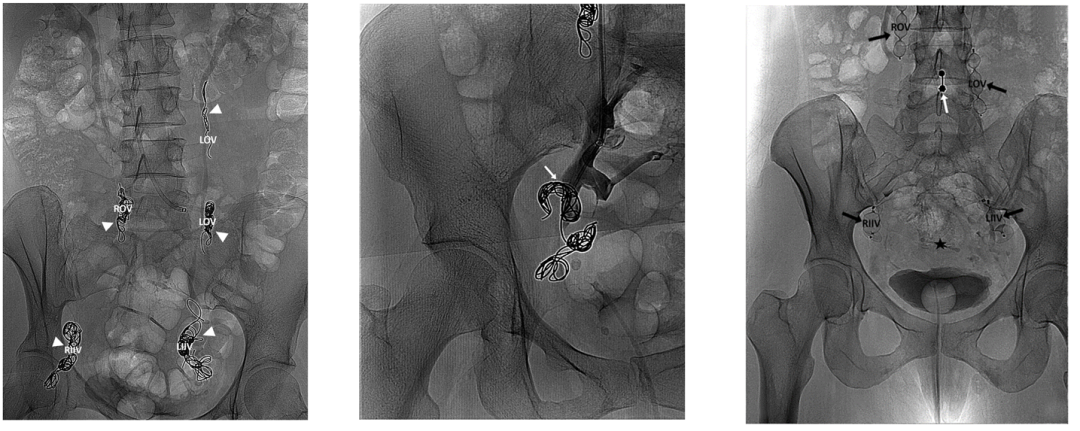

DSA分型系统

DSA分型

Ⅰ型:双侧瘤巢,对侧性腺静脉返流

Ⅱ型:单侧瘤巢,同侧髂内静脉返流

Ⅲ型:宫旁泄露,合并髂内下肢沟通

Ⅳ型:继发返流,肾或髂返流或畸形

Ⅴ型:其他特殊型

PeVD-髂内静脉同期栓塞

症状性PEP需要同期处理

示例(D-IIV)

示例(LOV+LCV)

节约型三明治技术--中山三板斧

结语

发现:CEAP分级有效甄选更大患病人群;

诊断:SVP分类明确PeVD诊断及病因探寻;

治疗:DSA分型明确治疗部位及栓塞方案;

瘤巢优先,反流兼顾;

固液结合,密实栓塞。

安全更经济;高效低复发。